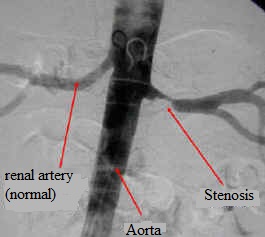

238. Hoffman BB Adrenoceptor Antagonist Drugs in: Basic and Clinical Pharmacology (10th edition), (Katzung BG, ed) McGraw-Hill Medical , New York, pp. 141-148, 2007.

282. Radermacher J Chavan A  Bleck J Vitzthum A Stoess B Gebel MJ Galanski M Koch KM Haller. Use of Doppler ultrasonography to predict the outcome of therapy for renal-artery stenosis. N Engl J Med 344(6): 410–417,2001.

283. Radermacher J, Haller H. The right diagnostic work-up: investigating renal and renovascular disorders. J Hypertens Suppl 21(2): S19–S24, 2003.

284. Venkatesan S Bilateral Renal Arterial Stenosis  http://www.youtube.com/watch?v=xeV3lmYi1Hk ; http://www.onlineheartcare.co.in/ .

285. Interventional Radiology in Action: Renal artery stenosis, http://www.lakeridgehealth.on.ca/patient_care/interventional_radiology/presentations/interventional/slide34.htm .